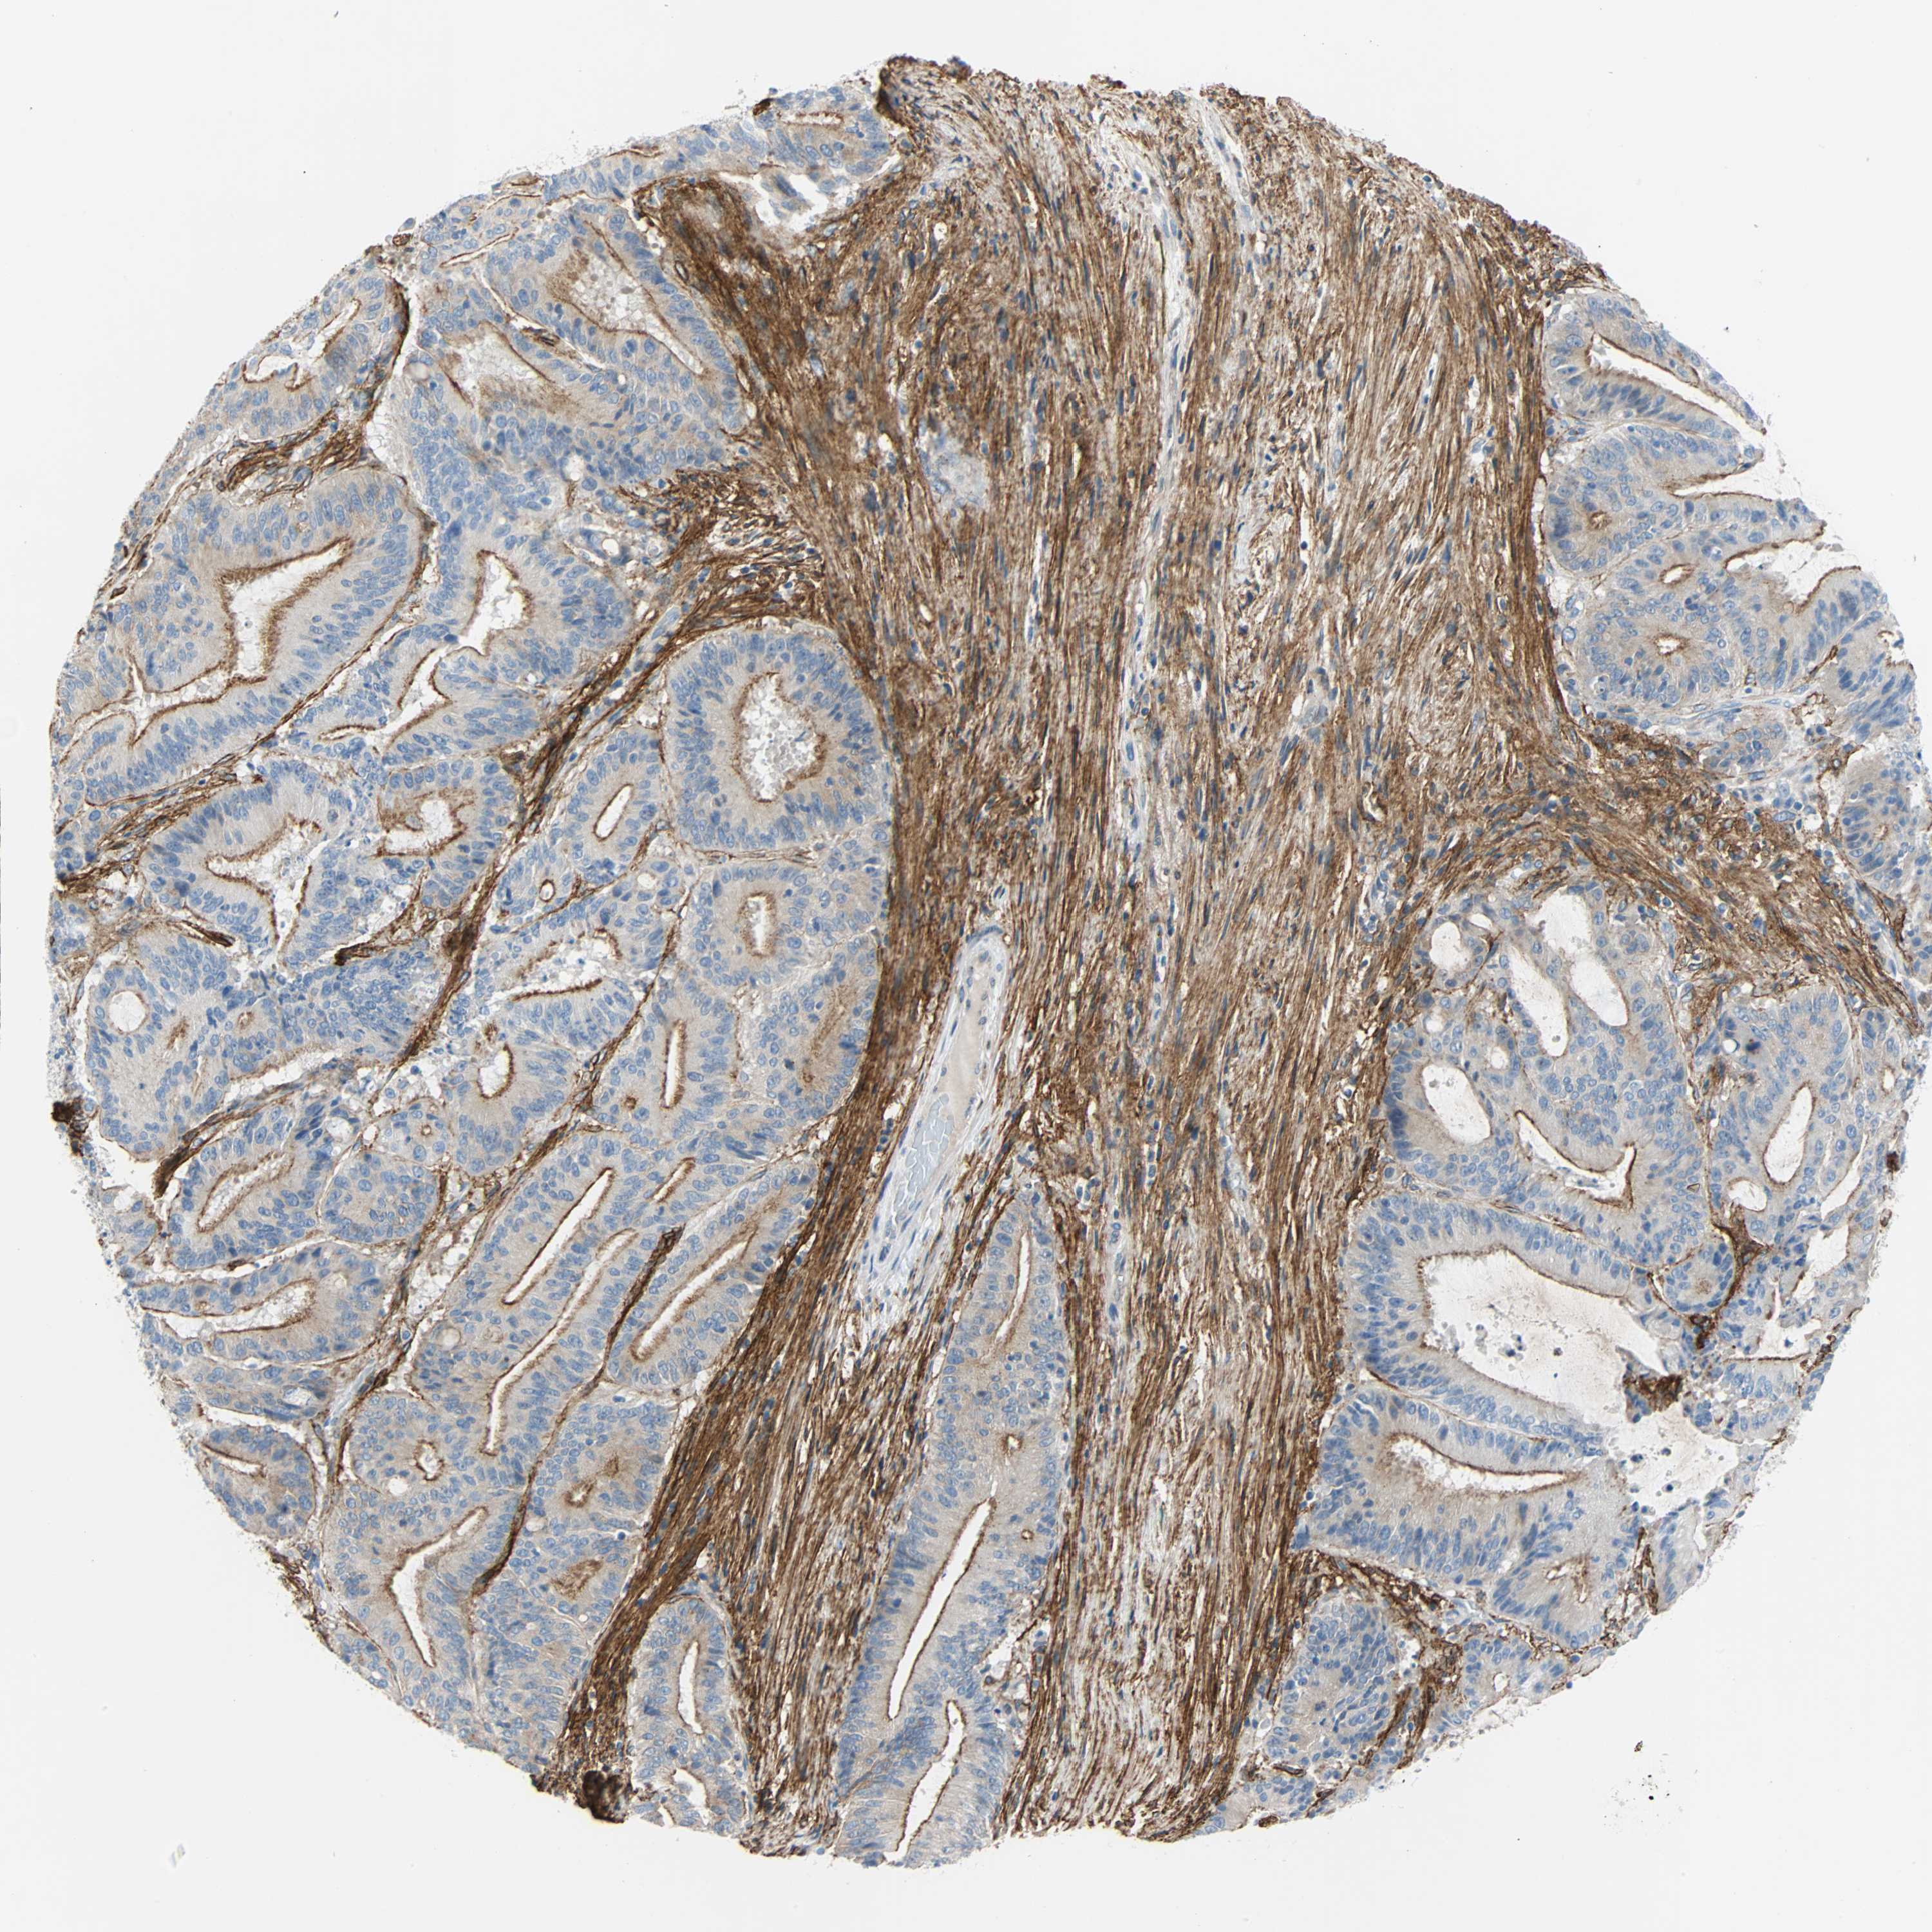

LIVER CANCER - Protein expressioni

A mouse-over function shows sample information and annotation data. Click on an image to view it in a full screen mode. Samples can be filtered based on level of antibody staining by selecting one or several of the following categories: high, medium, low and not detected. The assay and annotation is described here.

Note that samples used for immunohistochemistry by the Human Protein Atlas do not correspond to samples in the TCGA dataset.

Antibody stainingi

Antibody staining in the annotated cell types in the current human tissue is reported as not detected, low, medium, or high, based on conventional immunohistochemistry profiling in selected tissues. This score is based on the combination of the staining intensity and fraction of stained cells.

Each image is clickable and will lead to virtual microscopy that enables deeper exploration of all samples and also displays staining intensity scores, fraction scores and subcellular localization as well as patient and tissue information for each sample.

Antibody HPA007534

Antibody CAB008376

Staining

High

Medium

Low

Not detected

Intensity

Strong

Moderate

Weak

Negative

Quantity

>75%

75%-25%

<25%

None

Location

Nuclear

Cytoplasmic/membranous

Cytoplasmic/membranous,nuclear

Cholangiocarcinoma

Carcinoma, Hepatocellular, NOS